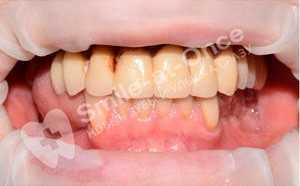

Чорный Станислав Владимирович: портфолио (25)

Имплантация

Для восстановления жевательных зубов потребовалось проведение имплантация полной челюсти по причине плохого состояния зубов на всей челюсти.